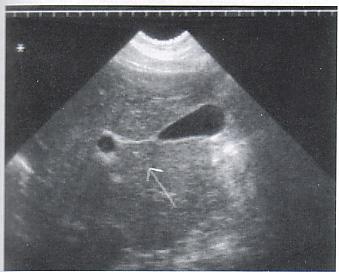

What is the sonographic appearance of Portal venous hypertension?

Portal vein measures greater than 13mm

Collateral

circulation

Flow reversal

Ascites

Hepatosplenomegaly